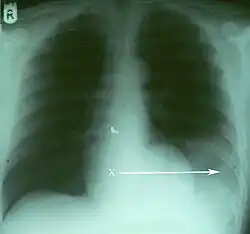

Verletzungen der Lunge können neben einer Lungenkontusion als Quetschverletzung Lungenrisse sein. Letztere führen zu einem Pneumothorax, wie er bei 10 bis 50 Prozent der Patienten mit Thoraxtrauma auftritt,[6] und gegebenenfalls zu einem Spannungspneumothorax. Blutungen in den Thorax hinein führen zu einem Hämatothorax. Bei einem Hämatopneumothorax treten sowohl ein Pneumo- als auch ein Hämatothorax in Kombination auf. Symptome sind zunächst Luftnot und je nach Ausmaß der Blutung auch Kreislaufinstabilität. Bei einem Pneumothorax kann sich insbesondere bei Ausbildung eines Spannungspneumothorax ein Hautemphysem bilden, das eine große Ausdehnung erreichen kann. Therapie ist eine Entlastung der Pleurahöhle mittels Thoraxdrainage auf der betroffenen Seite. Üblicherweise kommen kleinere intrathorakale Blutungen von alleine zum Stehen, so dass außer einer Drainage keine weiteren Maßnahmen notwendig werden. Eine Thorakotomie zur operativen Blutstillung kann bei einem initialen Blutverlust von mehr als 1.500 ml nach der Thoraxdrainage oder bei einem fortwährenden Blutverlust von mehr als 250 ml pro Stunde über mehr als vier Stunden erfolgen.[2][5]